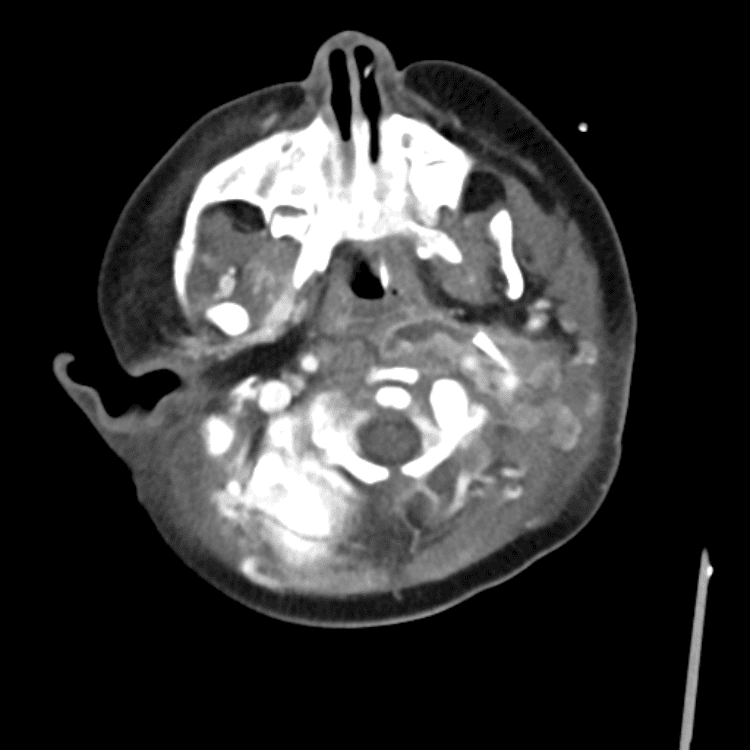

Head and Neck

Simulates call by including subtle or difficult cases and some normals.

27 cases